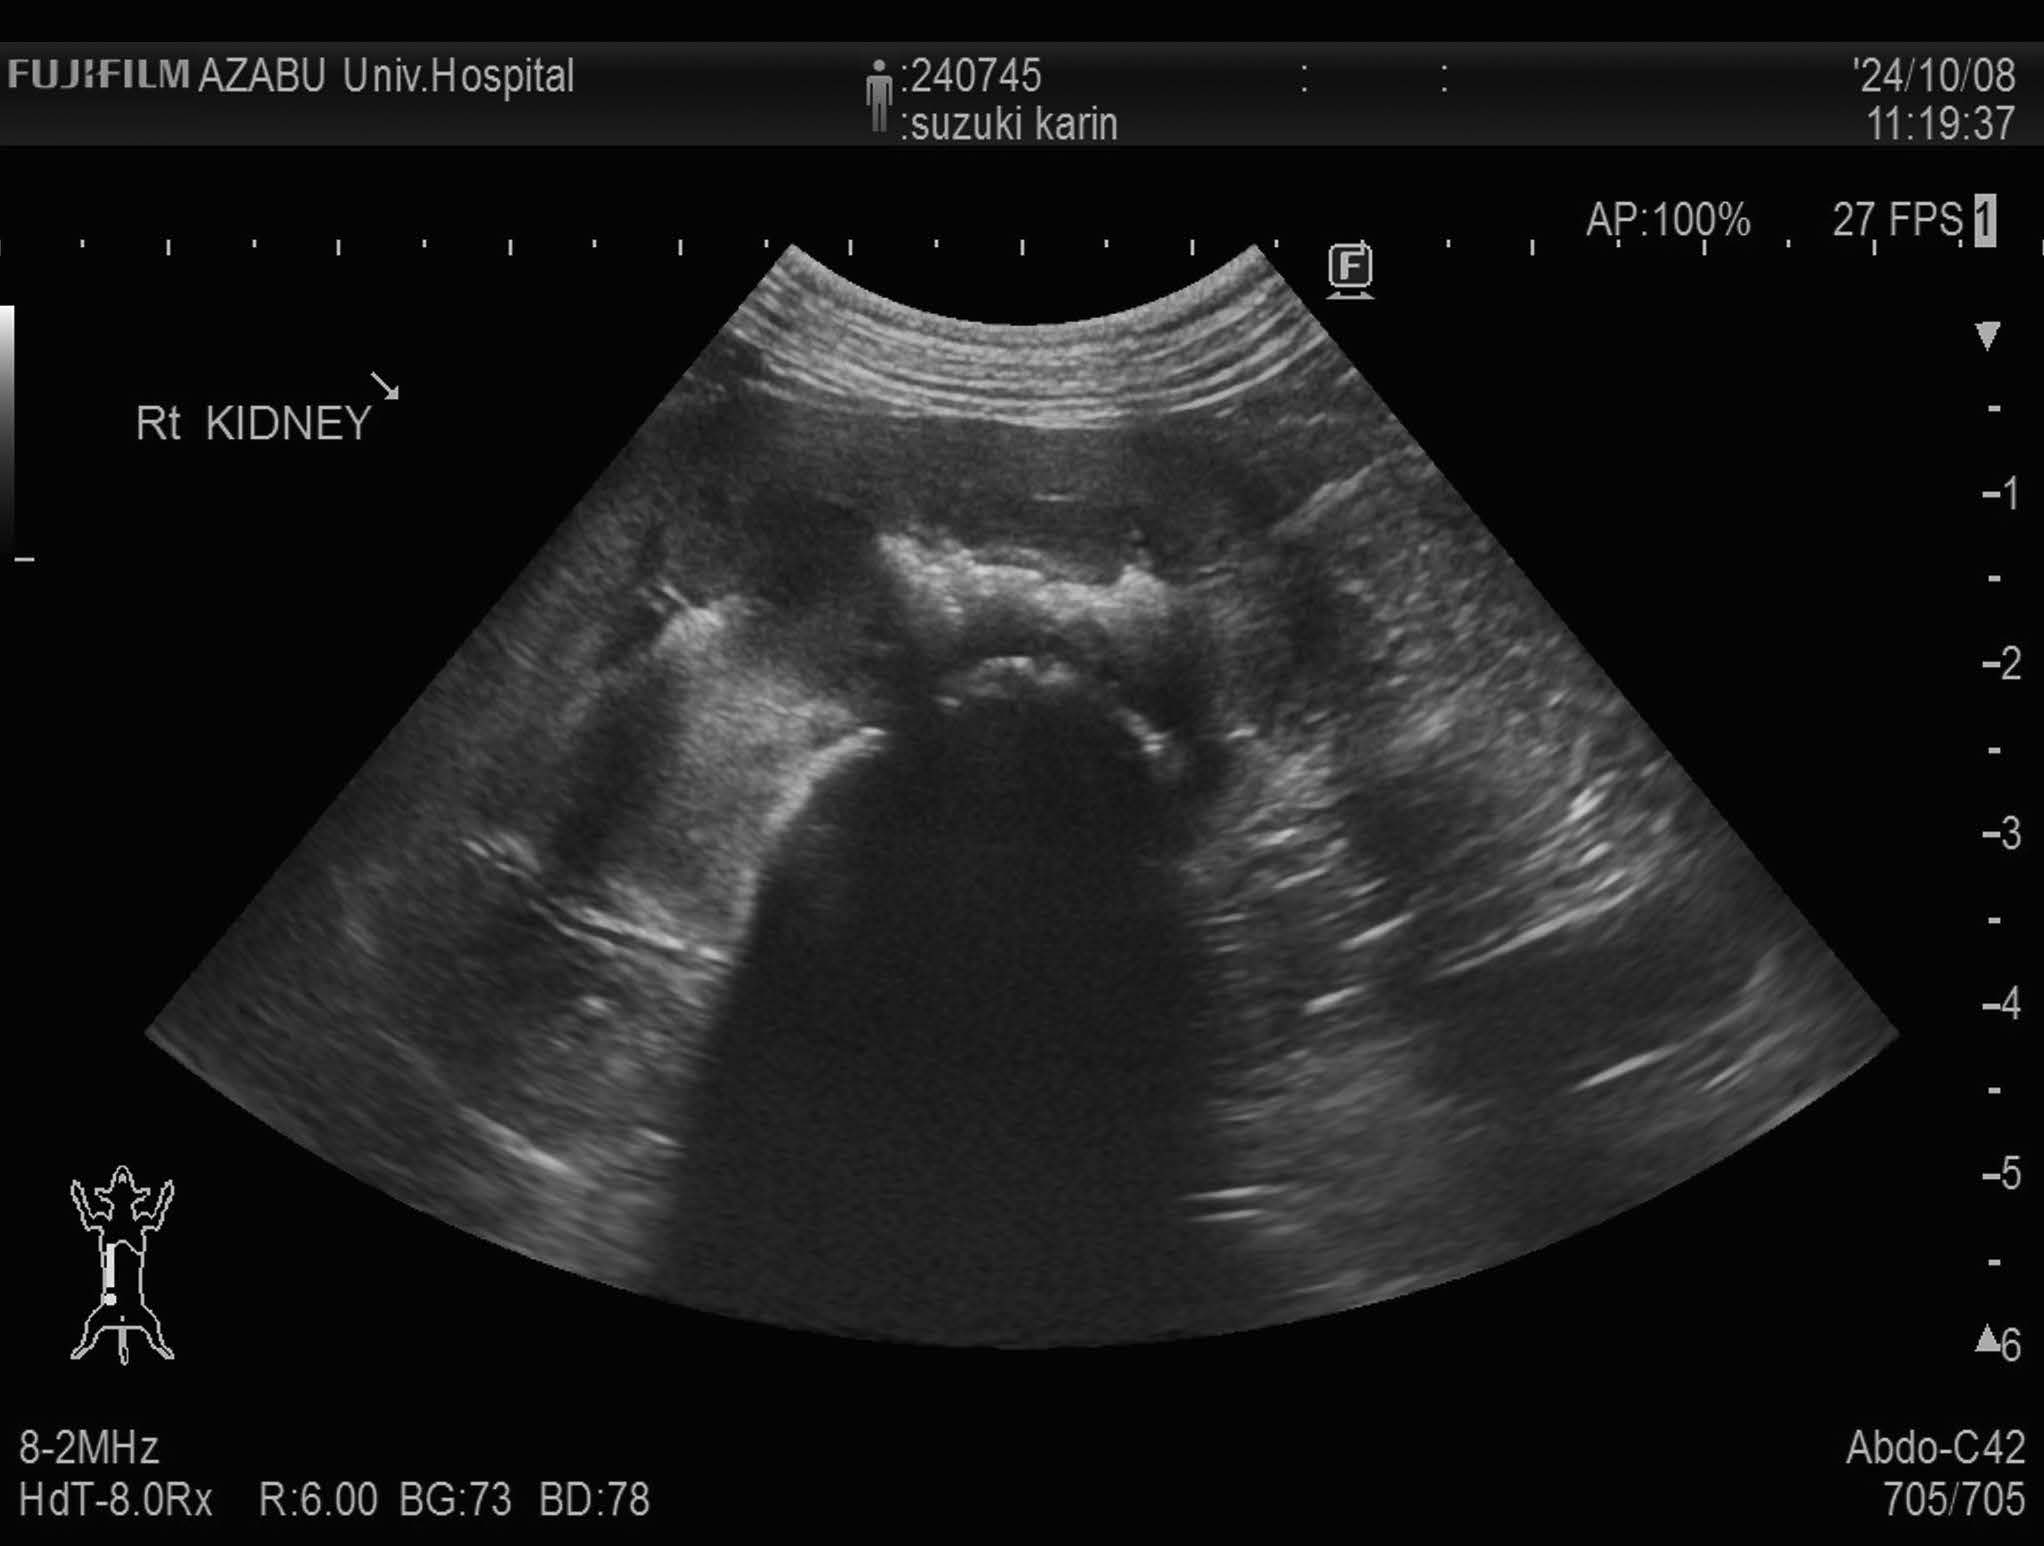

画像検査:腹部X 線検査では,肝サイズの低下と両腎にX 線不透過性の低い陰影が認められた(図1).腹部超音波検査では両側腎盂領域において,音響陰影を呈する高エコー構造物を認めた(図2).膀胱内には,高エコー源性の浮遊物及び沈渣が観察された.

図2 右腎臓の超音波検査画像

腎盂内を占拠する物体の音響陰影を認める.